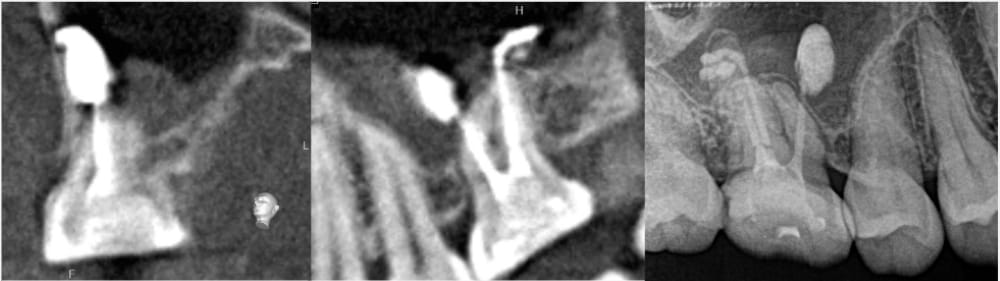

CT画像による三次元的比較

CT画像上でも、根尖部の骨の回復と漏出していた材料の消失が認められます。

今回の患者様の場合、飛び出た材料は治癒とともに自然と消失しました。(おそらく)吸収性の材料ではありませんが、身体の自己免疫機構が働き、異物として貪食され消失したと推測されます。多くの場合、根尖孔外の異物は残存したままで治癒します。そのため、今回のように綺麗に消失することは比較的稀であるといえるでしょう。また、もしも根尖孔外に飛び出た材料が原因で治癒しない場合には、外科的歯内療法の適応となります。